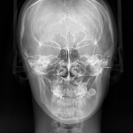

3D CT X-ray

顔面骨や顎関節の形態、歯の形状、

咬合状態などを立体的に把握し診断します。 -

咬合状態などを立体的に把握し診断します。